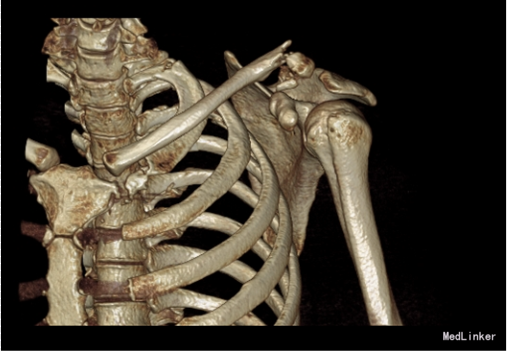

主诉:车祸外伤后9小时 患者自述2015-10-02车祸,导致左肩部受伤,疼痛,肿胀,肩关节活动受限,急送到苏家屯中心医院,诊断为“左锁骨骨折,气胸”,建议转院,为求进一步治疗来我院,诊断为“左锁骨骨折”,并收入我科,患者自受伤以来,无发热,呼吸略困难,无腹痛腹泻,饮食睡眠正常,大小便未见异常。

患者入院后完善相关检查,胸部CT报左气胸,请胸外科行闭式引流后,患者血氧约97%。择期行手术治疗。无其他手术禁忌症后行左锁骨骨折切开复位内固定术,术后3天后闭式引流液减少到10ml予以拔除。术后14天后出院。